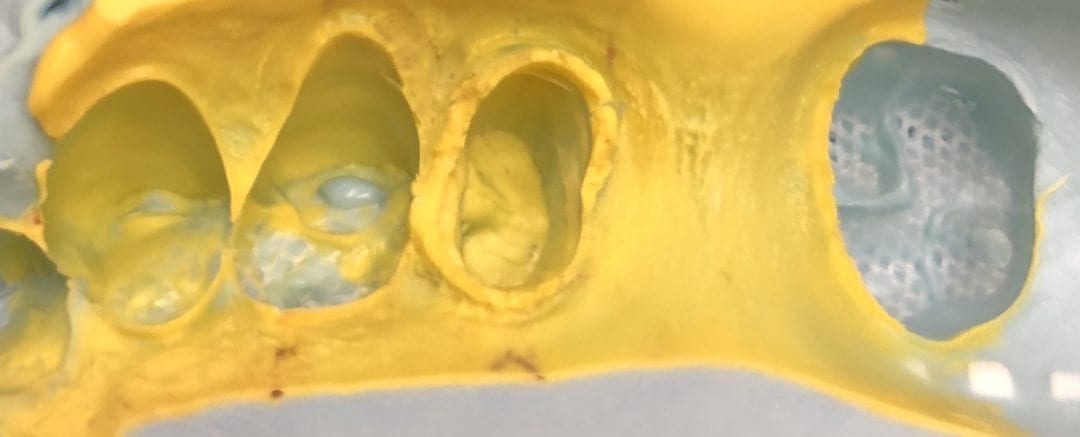

June 19, 2018If you are risk averse and want to take your first step into digital dentistry without altering a single thing you do in your practice, consider a desktop scanner, like […]